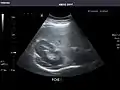

Spleen

Spleen: Normal in size.